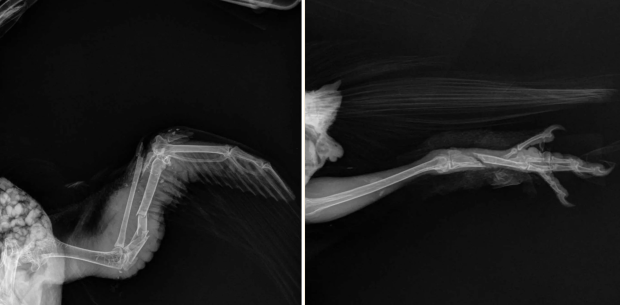

X-rays of Skye’s wing and leg

Skye went straight to Medical Center for Birds (MCFB) in Oakley the next morning. One of his wings was open — with exposed bone — so he was rushed into surgery to close and stabilize the wound. He also had a broken leg, which was splinted. We can’t know how long Skye was sitting there — scared, injured, and in pain — before he was found. We can be fairly certain his owner didn’t bother looking for him.